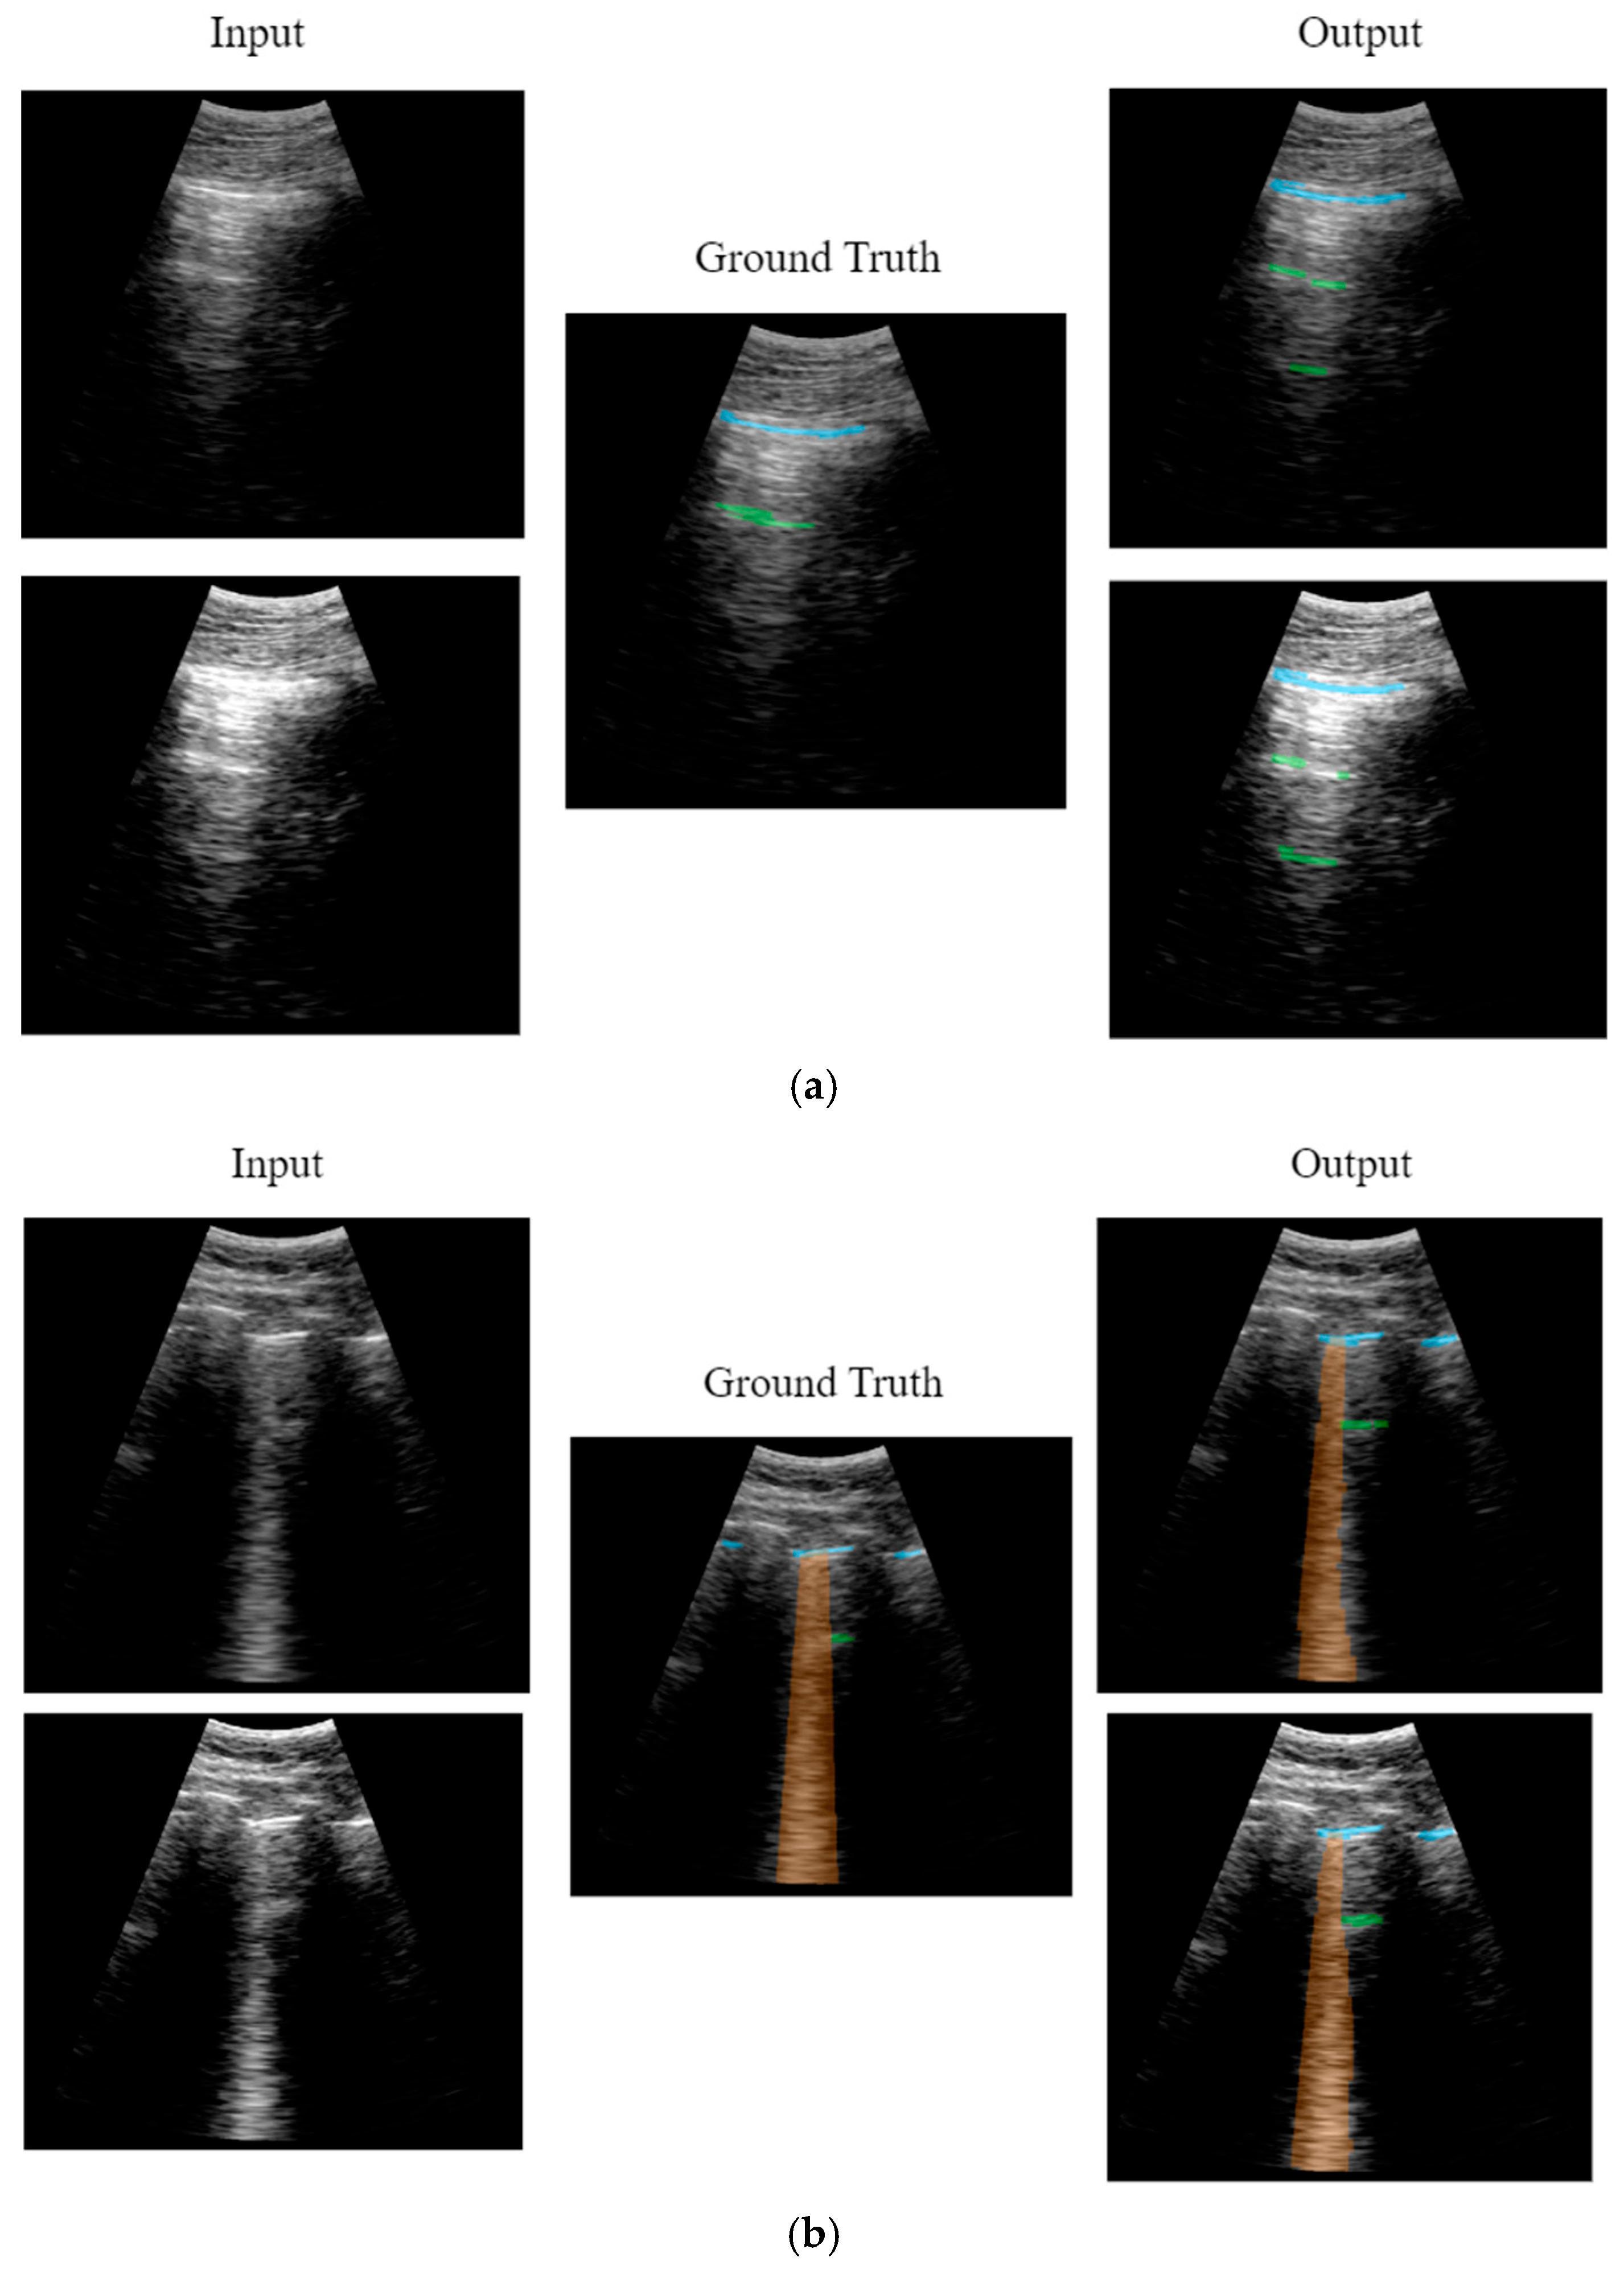

2.2.2. Neural Network Output Data

Labelling Tools

CNN Output

3.1. Model Results